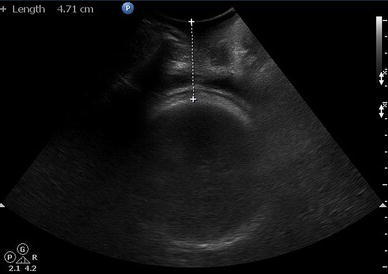

All eligible women admitted for delivery who were planned for induction of labour underwent imaging procedure. A 3.5-MHz abdominal probe was covered with sterile glove and was placed on the perineal area between two ischial tuberosities and was directed towards the presenting part. The shortest distance from the outer bony limit of foetal skull to skin surface of the perineum in a transverse view was measured to represent FHPD (Fig. 1). Following transperineal scan, transvaginal ultrasound was performed using 5.5-MHz ultrasound probe to measure cervical length. After the scans, pervaginal examination was performed to assess the various components of modified Bishop score (min 0, max 10). If cervix was found unfavourable, induction of labour was using dinoprostone gel 0.5 mg (6 hourly induction, maximum 3 doses, if patient did not get into active labour, then induction was considered unsuccessful) or else oxytocin drops in cases where cervix was nicely favourable. The patients were followed up till delivery.

Fig. 1.

Caliper placement to calculate FHPD